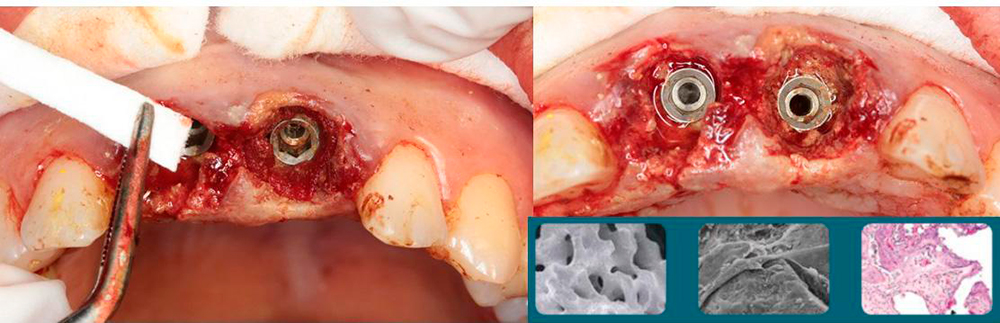

Premium Spiral Implants placement

Syntoss bone graft and Zenoss matrix membrane placing